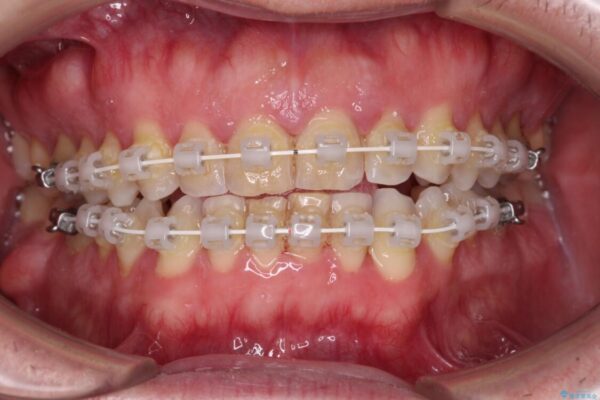

治療途中

• 前歯でものを噛みきりたい 目立たない装置でのワイヤー矯正 治療途中画像

前歯の非接触改善は、インビザラインの得意とするところですが、マウスピース矯正は絶対に継続できないとのことで、ワイヤー装置にて矯正治療を行うこととしました。

舌の突出癖が改善されない限り、非接触改善は見込めないため、トレーニングを徹底するように指示しました。